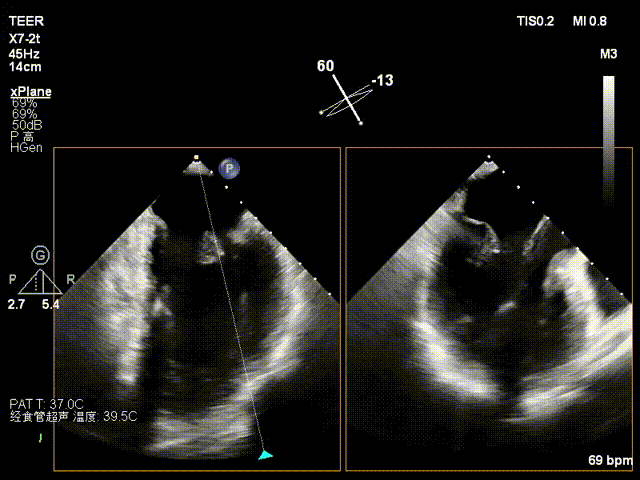

术前影像

X-plane2区

X-plane 1区

X-plane 2区